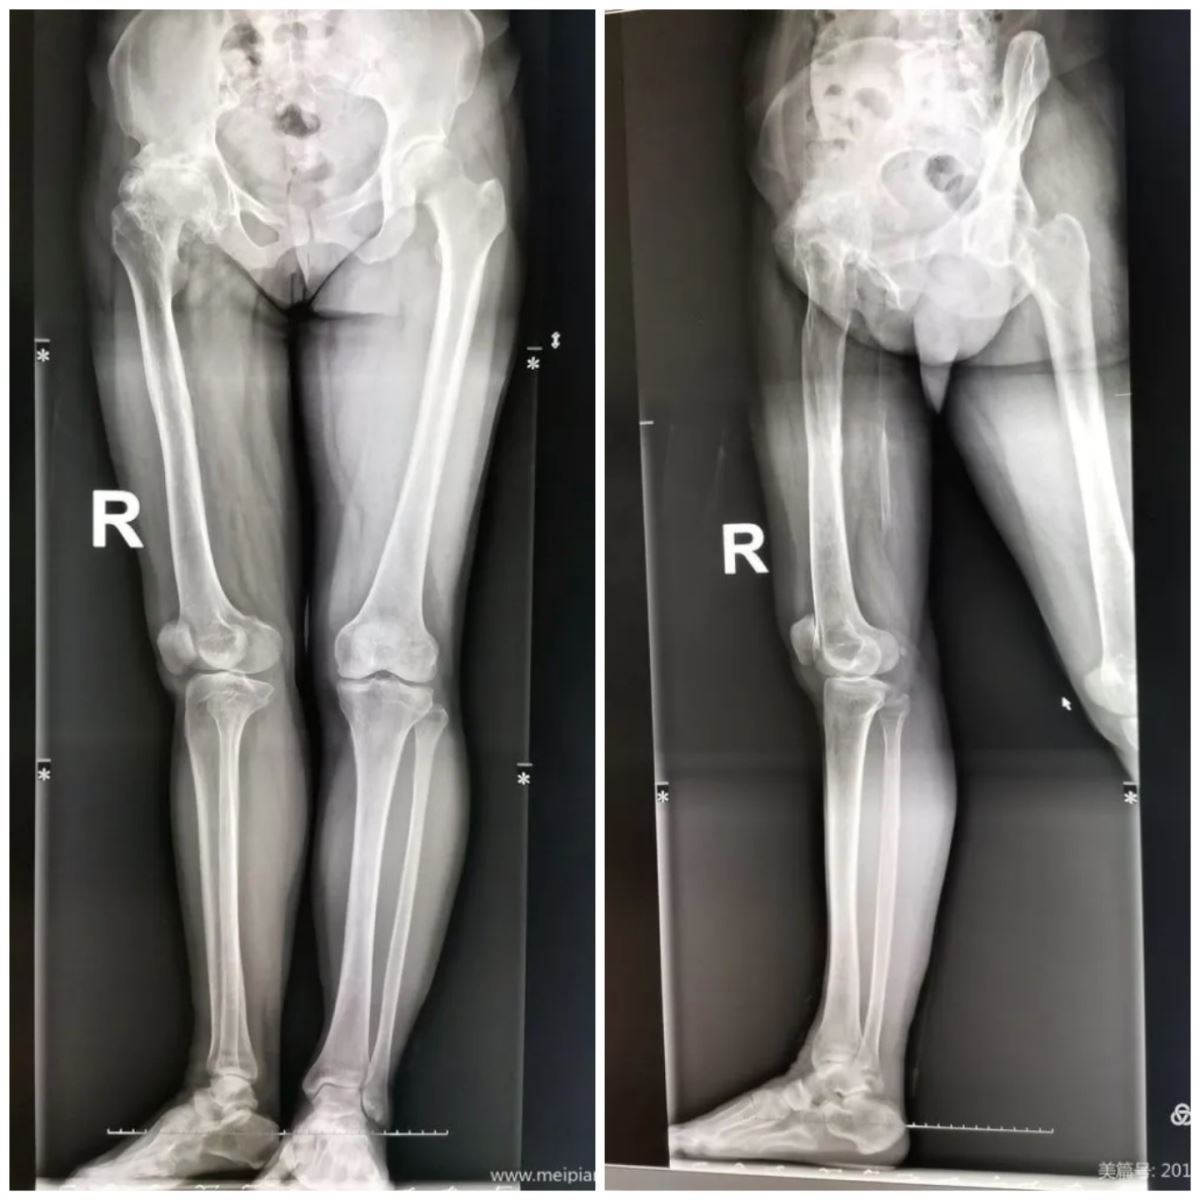

第一例患者男性,28岁,腰痛及双侧髋部肿痛3年,家中活动受限1年。1年前在盛京医院被诊断为“强直性脊柱炎、双侧股骨头坏死”,该院予以行股骨头减压术,当时患者症状缓解,但疼痛依然存在,后期症状逐渐加重,故来我院就诊。入院查体脊柱后凸畸形,前倾约20°,右髋关节僵直于屈曲50°,左髋关节僵直于30°,均无外展、内收、内旋及外旋功能,髋关节周围肌群肌肉中度萎缩,双下肢感觉功能未见异常通过X线、CT等辅助检查,该患者被诊断为“强直性脊柱炎、双侧股骨头坏死、融合髋”。本次手术难点为:1.体位摆放及消毒,关节手术相对于其他骨科手术要求更高,该病人融合髋几乎无任何外展功能,增加了本次手术难度;2.如何对股骨颈截骨并取下股骨头,普通关节置换只要屈曲、外展、外旋髋关节即可显露股骨颈,而该患者融合髋,已无上述功能,如何将股骨颈显露并将股骨头与髋臼分离是本次手术第二个难点;3.髋臼的显露,髋臼已与股骨头表面愈合,解剖学间隙很难在出血及周围组织遮挡情况下去分辨明确,因此探寻“真臼”是本次手术的第三个难点;4.患者腰骶角20°,存在严重骨盆后倾,如何调整前倾角是决定术后是否成功的关键; 5.手术时间及出血量估计,患者手术难度大,如何减少术中出血量、减少手术时间也是十分关键的问题。胡中申主任组织骨五团队进行讨论,通过对X线及CT片的深入分析,详细了解了股骨髓腔形态、关节融合情况、估计股骨颈截骨位置、假体选择及安放位置。针对上述问题提出术前计划:1.该患尽管双侧髋关节融合,但双下肢可分开30°,利用这30°间隙由双人抬腿、双人消毒铺单,避免造成暴力骨折;2.采用后外侧入路,通过对股骨颈多次、多平面截骨,将髋关节恢复至常规显露股骨颈方法,可以将股骨头暂时保留在髋臼内(避免坐骨神经损伤),而后用骨刀分次利用“蚕食”法,化整为零,将视野内股骨头取出;3.利用C型臂,在多次髋臼锉作用下,结合术前X线寻找“真臼”位置;4.根据联合前倾角及假体股骨颈前倾角,最后确定髋臼前倾角及外展角;5.如果耗时时间较长、出血量多,可以分两次置换手术治疗。有了周密的术前计划和胡主任多年的临床手术经验,胡主任率领的骨五科团队在手术与麻醉科的密切配合下,历时4个小时,成功为患者一次完成双侧关节置换术。

第二例患者女性,50岁,右髋部疼痛伴活动障碍5年,加重1年后在当地医院治疗,被诊断为“右侧股骨头坏死”,予以止痛及改善微循环药物治疗,症状未见缓解并逐渐加重。既往患者14岁时外伤致右侧股骨近端骨折,用夹板保守治疗,而后出现右下肢外旋90°畸形愈合。来我院骨五科就诊,入院查体右下肢外旋90°短缩3.0CM畸形,右侧髋关节屈曲90°,后伸0°,无内收及外展功能,右髋关节周围及下肢肌肉存在轻度肌萎缩,双下肢感觉功能未见异常。通过病史及X线、CT等辅助检查,我院对该患者诊断为:1.右侧股骨头坏死;2.陈旧性股骨近端骨折畸形愈合。本次手术难点为:1. 股骨近端畸形愈合,股骨前倾角改变;2.右下肢存在不等长,需要纠正。胡主任组织科室医生开展讨论,通过对X线及CT片的深入分析,详细了解右侧股骨髓腔形态、假体选择及安放位置。针对上述问题提出术前计划:1.选择Wargnar假体,调整股骨前倾角,如果术中调整股骨前倾角失败则可以考虑行股骨粗隆下截骨治疗;2.根据术前X线检查下肢不等长为股骨头坏死致解剖学间隙消失右侧髋关节骨性关节炎引起,通过调整组配假体股骨颈长度即可以调整右下肢肢体长度。术中调整股骨前倾角取得成功,选择假体大小合适,并未出现神经症状,患者术后对肢体长度和步态均满意。